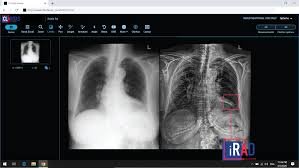

This clearance from TGA in Australia further expands the reach and use of Claritas iPET™, already cleared and used in several jurisdictions. This software tool which is agnostic to equipment type and manufacturer, and which integrates into existing hospital systems, is being used to enhance noisy and unclear Positron Emission Tomography (PET) scans for improved visibility and sharpness. The methods implemented in Claritas iPET™ ensures fine lesions are not lost on enhancement, SUV values are maintained, and no artifacts are introduced.

Hospitals and clinics use the Claritas iPET™ capabilities to process PET scans obtained with reduced scan time and/or reduced isotope dosage to yield diagnostic quality scans. Thus, increasing scan throughput and providing a much-improved patient experience, by reducing radiation exposure and scan time. Claritas iPET™ has features that enables the use of CT or MRI data to be used as an overlay to PET data for additional information and clarity.